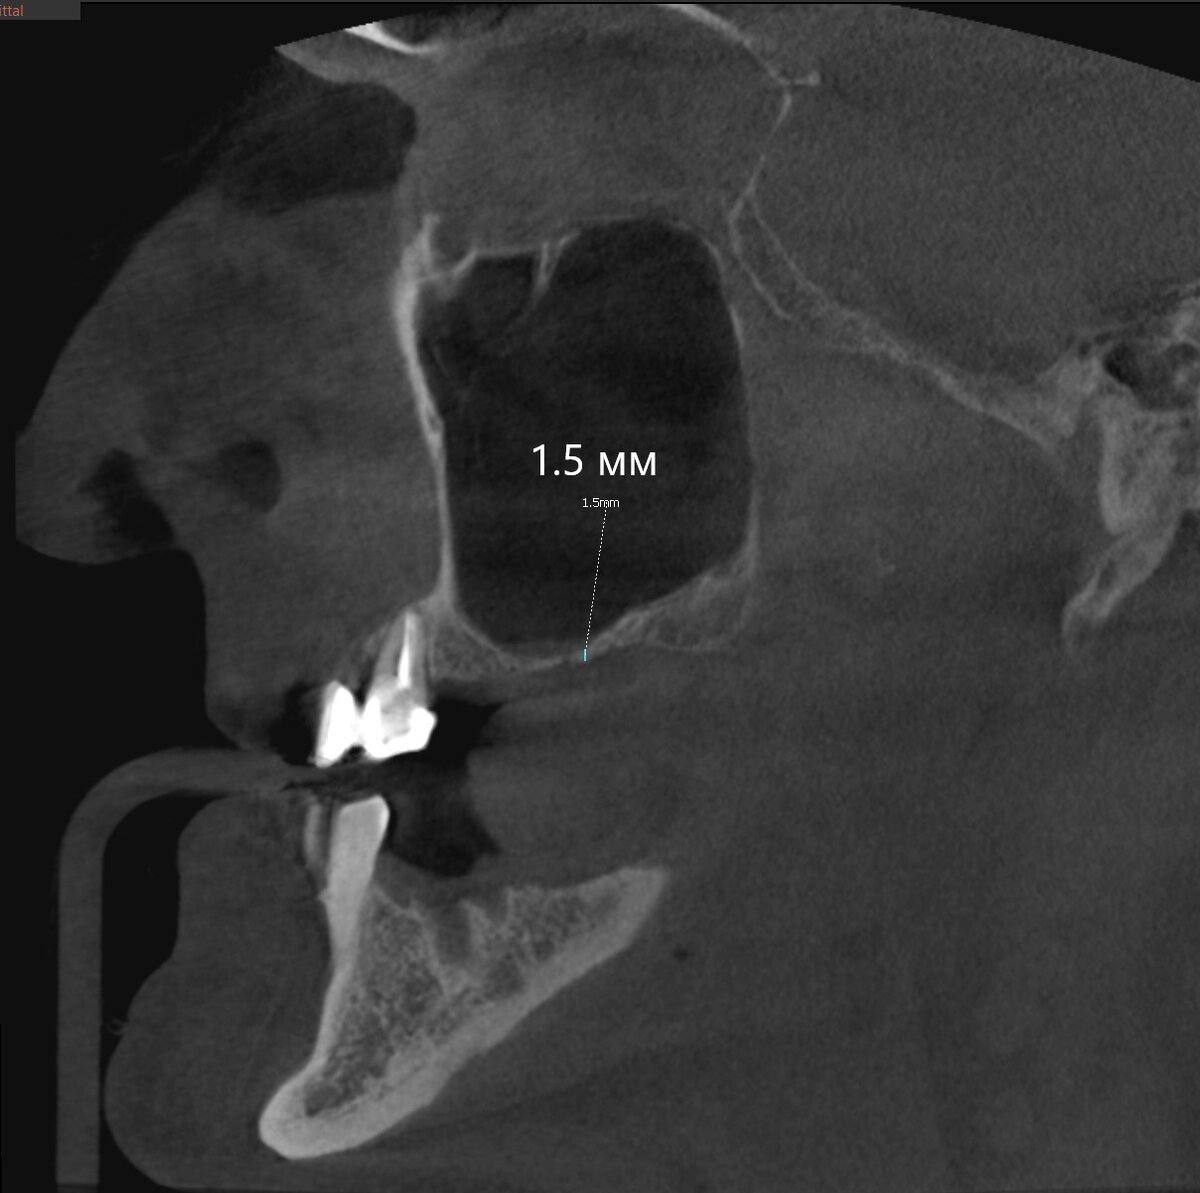

А чем же? Находим причинный зуб:

Есть большая вероятность, что содержимое - гнойное.

Мы сами дистанционно связались с доверенным ЛОР-врачом и поинтересовались, опасно ли проводить синус-лифтинг справа, когда такая засада слева. ЛОР оценил протоки и дал добро.

Зуб с противоположной стороны (2.6) был удалён, сообщение с пазухой минимальное и имплантолог не стал расширять доступ. Проверил дно костной лунки и отправил пациента на КЛКТ. Вот результат:

А "киста" сдулась. И сделала она это ещё ДО удаления зуба, 100%. Подозрение на ретенционную "кисту", такую же, как была описана мною вот в этом случае:

Гноя не выявлено, в общем. Это очень хорошо.